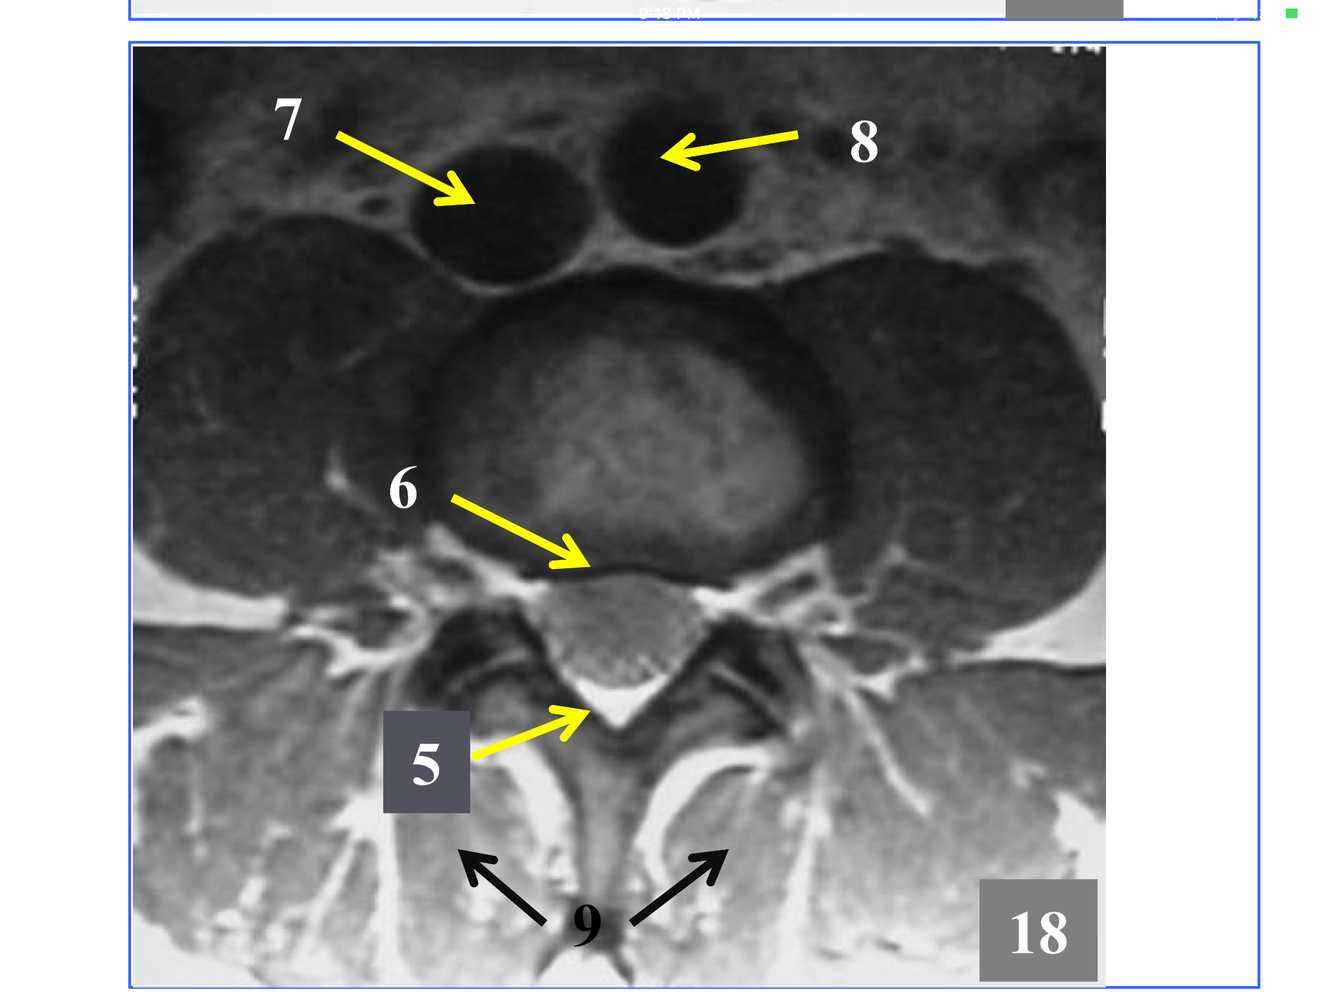

* The stack of inferior and superior articulating processes, and the zygapophyseal joints they form

*Comprised of the inferior and superior articulating processes, and the zygapophyseal joints they form